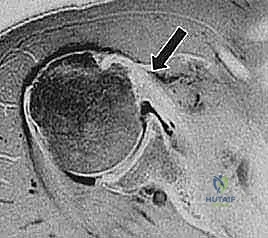

| الموجات فوق الصوتية (Ultrasound) | فحص ديناميكي للأوتار أثناء حركة الكتف، رخيصة وسريعة. | كفحص مبدئي لتقييم الكفة المدورة ووتر ذات الرأسين. | متوسطة إلى جيدة، تعتمد على مهارة الفاحص. |

| الرنين المغناطيسي (MRI) | المعيار الذهبي. يظهر تفاصيل الأنسجة الرخوة، حجم التمزق، وتراجع العضلة. | لتأكيد التشخيص والتخطيط الدقيق للعملية الجراحية. | دقة ممتازة وتفاصيل ثلاثية الأبعاد. |

2. تنظير المفصل الاستكشافي الدقيق (Diagnostic Arthroscopy)

يقوم الدكتور هطيف بعمل شقوق صغيرة جداً (ثقوب بحجم ثقب المفتاح) حول الكتف. يتم إدخال كاميرا عالية الدقة (4K) وأدوات جراحية دقيقة. يتم ضخ سائل معقم داخل المفصل لتوسيعه وتوفير رؤية واضحة. يبدأ الجراح بفحص المفصل بالكامل من الداخل لتقييم حجم التمزق، حالة الغضاريف، ووضع وتر العضلة ذات الرأسين.